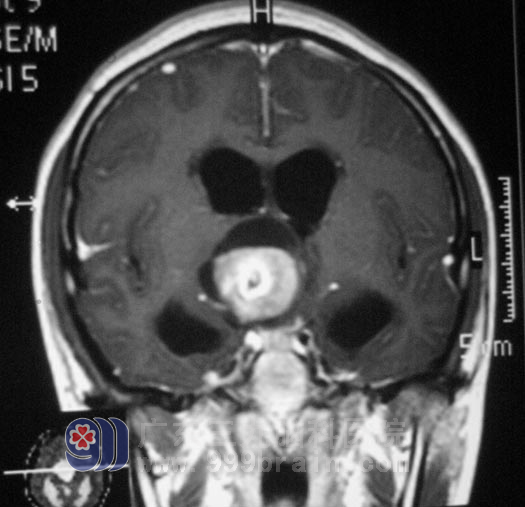

小敏,两月前出现反复阵发性头痛,伴有恶心、呕吐,偶有头晕,母亲带着她到当地医院就诊,颅脑MR检查提示:三脑室占位性病变。

完善相关检查后,5月10日,由鲁明主任主刀,在全麻下行三脑室占位性病变切除术,术中见肿瘤呈灰白色,边缘质硬,中心部位质软,血供一般,呈鱼肉样,在显微镜下予肿瘤切除,手术过程顺利。手术后小敏的情况一天一天好转,现已经出院在家。术后病理结果为:(第三脑室)毛细胞型星形细胞瘤,WHO I级。